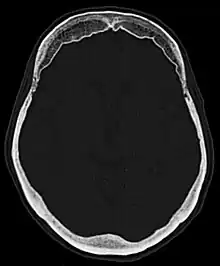

Hyperostosis frontalis interna in a 74-year-old woman

Hyperostosis frontalis interna is a common, benign thickening of the inner side of the frontal bone of the skull. It is found predominantly in women after menopause and is usually asymptomatic. Mostly frequently it is found as an incidental finding discovered during an X-ray or CT scan of the skull.

Hyperostosis frontalis at CT